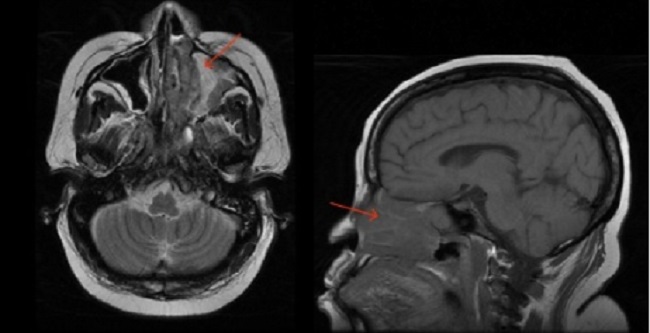

Дегенерация синуса

Дегенерация синуса 83 фото